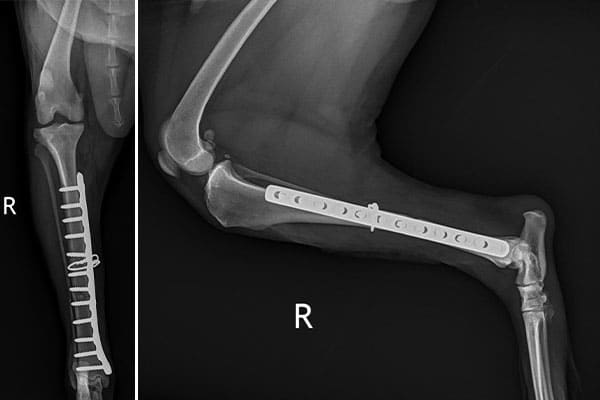

- Evaluation for broken bones or trauma

SAVC utilizes a modern digital radiology system that allows us to gather high quality, diagnostic images rapidly with little stress to your pet. Within seconds images are available for review. Also when utilizing a digital system, we can quickly share radiographic images to boarded veterinary radiologists, who are uniquely qualified to evaluate radiographs and diagnose disease from such. Our digital system allows us utilize telemedicine and veterinary specialists to provide your pet the best care possible within hours.

Radiology remains an essential tool to the veterinarian but SAVC has taken radiology to the next level but also offering ultrasound and CT imaging to complement our radiology service.